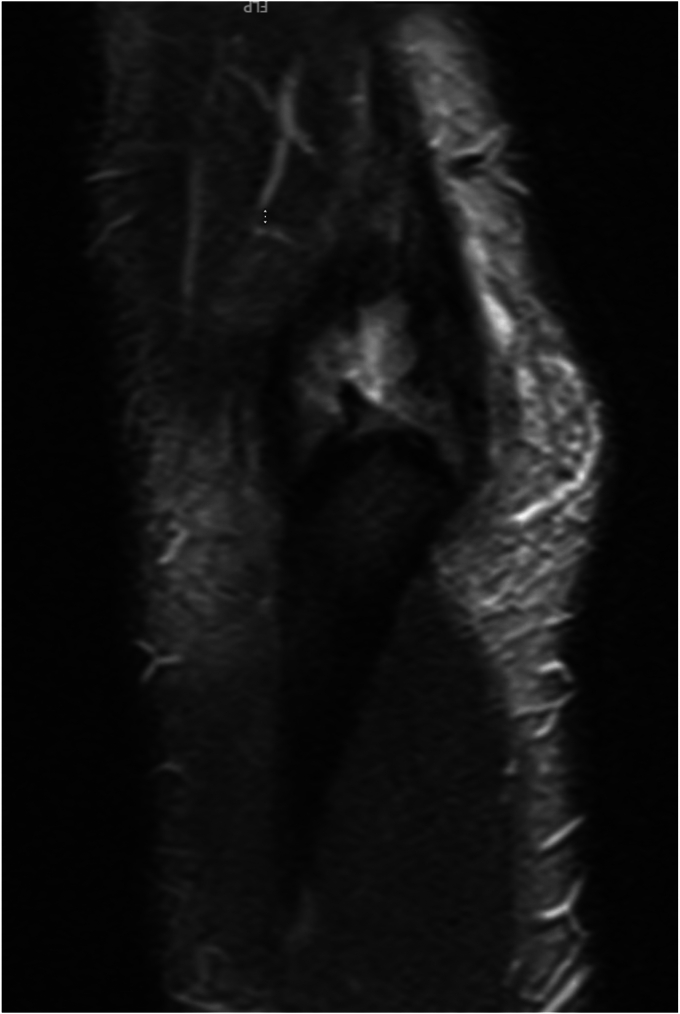

Initial anteroposterior and lateral radiographs of the right elbow demonstrated chronic calcification of the triceps tendon posteriorly (Figs. 1 and 2). A T2-weighted magnetic resonance imaging (MRI) of the right elbow was then performed in order to further evaluate the injury, which was interpreted and reviewed by a fellowship-trained shoulder and elbow orthopedic surgeon. T2-weighted MRI of the right elbow demonstrated a full-thickness tear of the triceps tendon with approximately 5 centimeters of retraction off the distal insertion of the olecranon process with surrounding hyperintense T2 signal (Figure 3, Figure 4, Figure 5). No intra-articular effusion or loose bodies were present, and there was no significant radiocapitellar or ulnohumeral arthrosis. No other abnormalities were noted on the MRI.

Figure 5.

Preoperative magnetic resonance imaging. Coronal T2-weighted MRI of the right elbow with evidence of full-thickness tear of the triceps tendon.